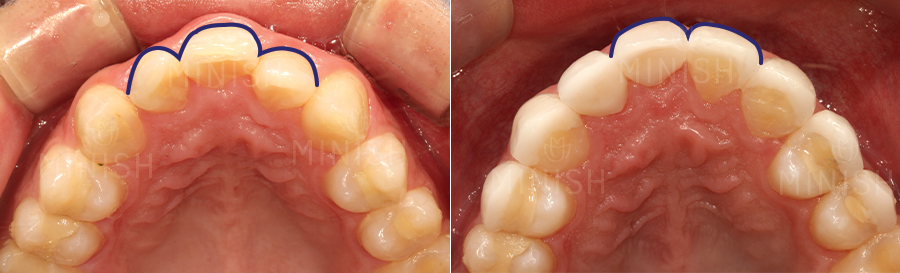

두 번째 앞니(측절치)를 이용한 결손치 복원

* 질환: 선천적 결손치(#21, #35), 치아비대칭, 교합 틀어짐

* 촬영일자: Before 2022.03.16 After 2022.04.08

* 실치료기간: 5일

기존 앞니와 잘 어우러질 수 있도록 잇몸 형태와 치아의 크기, 색상까지 여러 측면을 고려해 진행하였습니다. 그 중에서도 치은절제술 및 핑크미니쉬를 통해 잇몸 라인의 대칭을 맞춰주었는데요. 부어있던 잇몸이 빠른 시일 내 건강해질 수 있도록 함은 물론, 자연스러운 잇몸 형태로 개선이 되었습니다. 또한 교합 힘에 의해 잇몸이 내려가 있었던 부분도 핑크미니쉬로 하여금 연분홍빛 잇몸으로 개선되었고, 조화롭고 건강한 잇몸 형태를 띠게 되었습니다.

이OO님의 경우 결손치로 인해 치아들이 쏠리면서 치아비대칭도 심각했는데요. 완벽한 대칭 개선에는 어려움이 있었지만, 미니쉬를 통해 앞니를 복원하고 치아비대칭도 자연스럽게 개선이 되었습니다.

아랫니 전면을 틈새없이 코팅해주어 자연치아는 건강하게 보호해주면서 전체적인 치열이 고르게 배열된 것이 보이죠. 뿐만 아니라 색상과 질감까지도 개선되어 심미적으로도 한 층 좋아졌습니다.